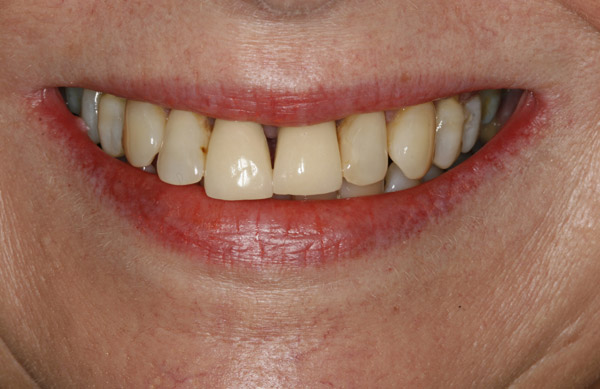

Thank you to our patients that have allowed us to show examples of our work

Have a look at just some of the many patient examples we have captured from BEFORE and AFTER their treatments and cosmetic surgeries.

From Whitening to Veneers, Fillings to Cosmetic Teeth Makeovers, here are some examples of the work that Dr. Dadabhai has provided to his patients to give them a more confident smile and a positive, pain free feeling.

Much of the work we carry out is to relieve pain and of course maintain the health of your teeth and gums, but many of our patients now ask for Cosmetic work to give them a more confident smile.

Cosmetic support has improved hugely over the last few years. Book a Consultation with Dr Dadabhai and he will prescribe a course of treatment to complete your perfect SMILE transformation.

Slide your computer mouse or finger (touch screens) over the image to view BEFORE and AFTER comparison.